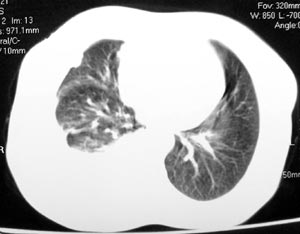

患者女性,52岁,胸闷,咳嗽,活动后气短2个月,加重1周.血常规:wbc10.28,rbc4.62,hgb135,plt267.胸水

常规:李凡他(+).胸水ada:68.1,ldh:303.6.胸水脱落细胞:未查到肿瘤细胞.

双肺纹理增多增粗,右上肺可见纤维条索致密影,右肺门粗浓,右侧胸腔积液,纵隔未见明显肿大淋巴结,

考虑肺部感染?

图像不是太好,但可以见到下列恶性征象:

1 单侧肺门增大

2 纵隔侧胸膜明显增厚

3 肋胸膜结节影

结合纵隔略宽、单侧胸水首先考虑肺癌。